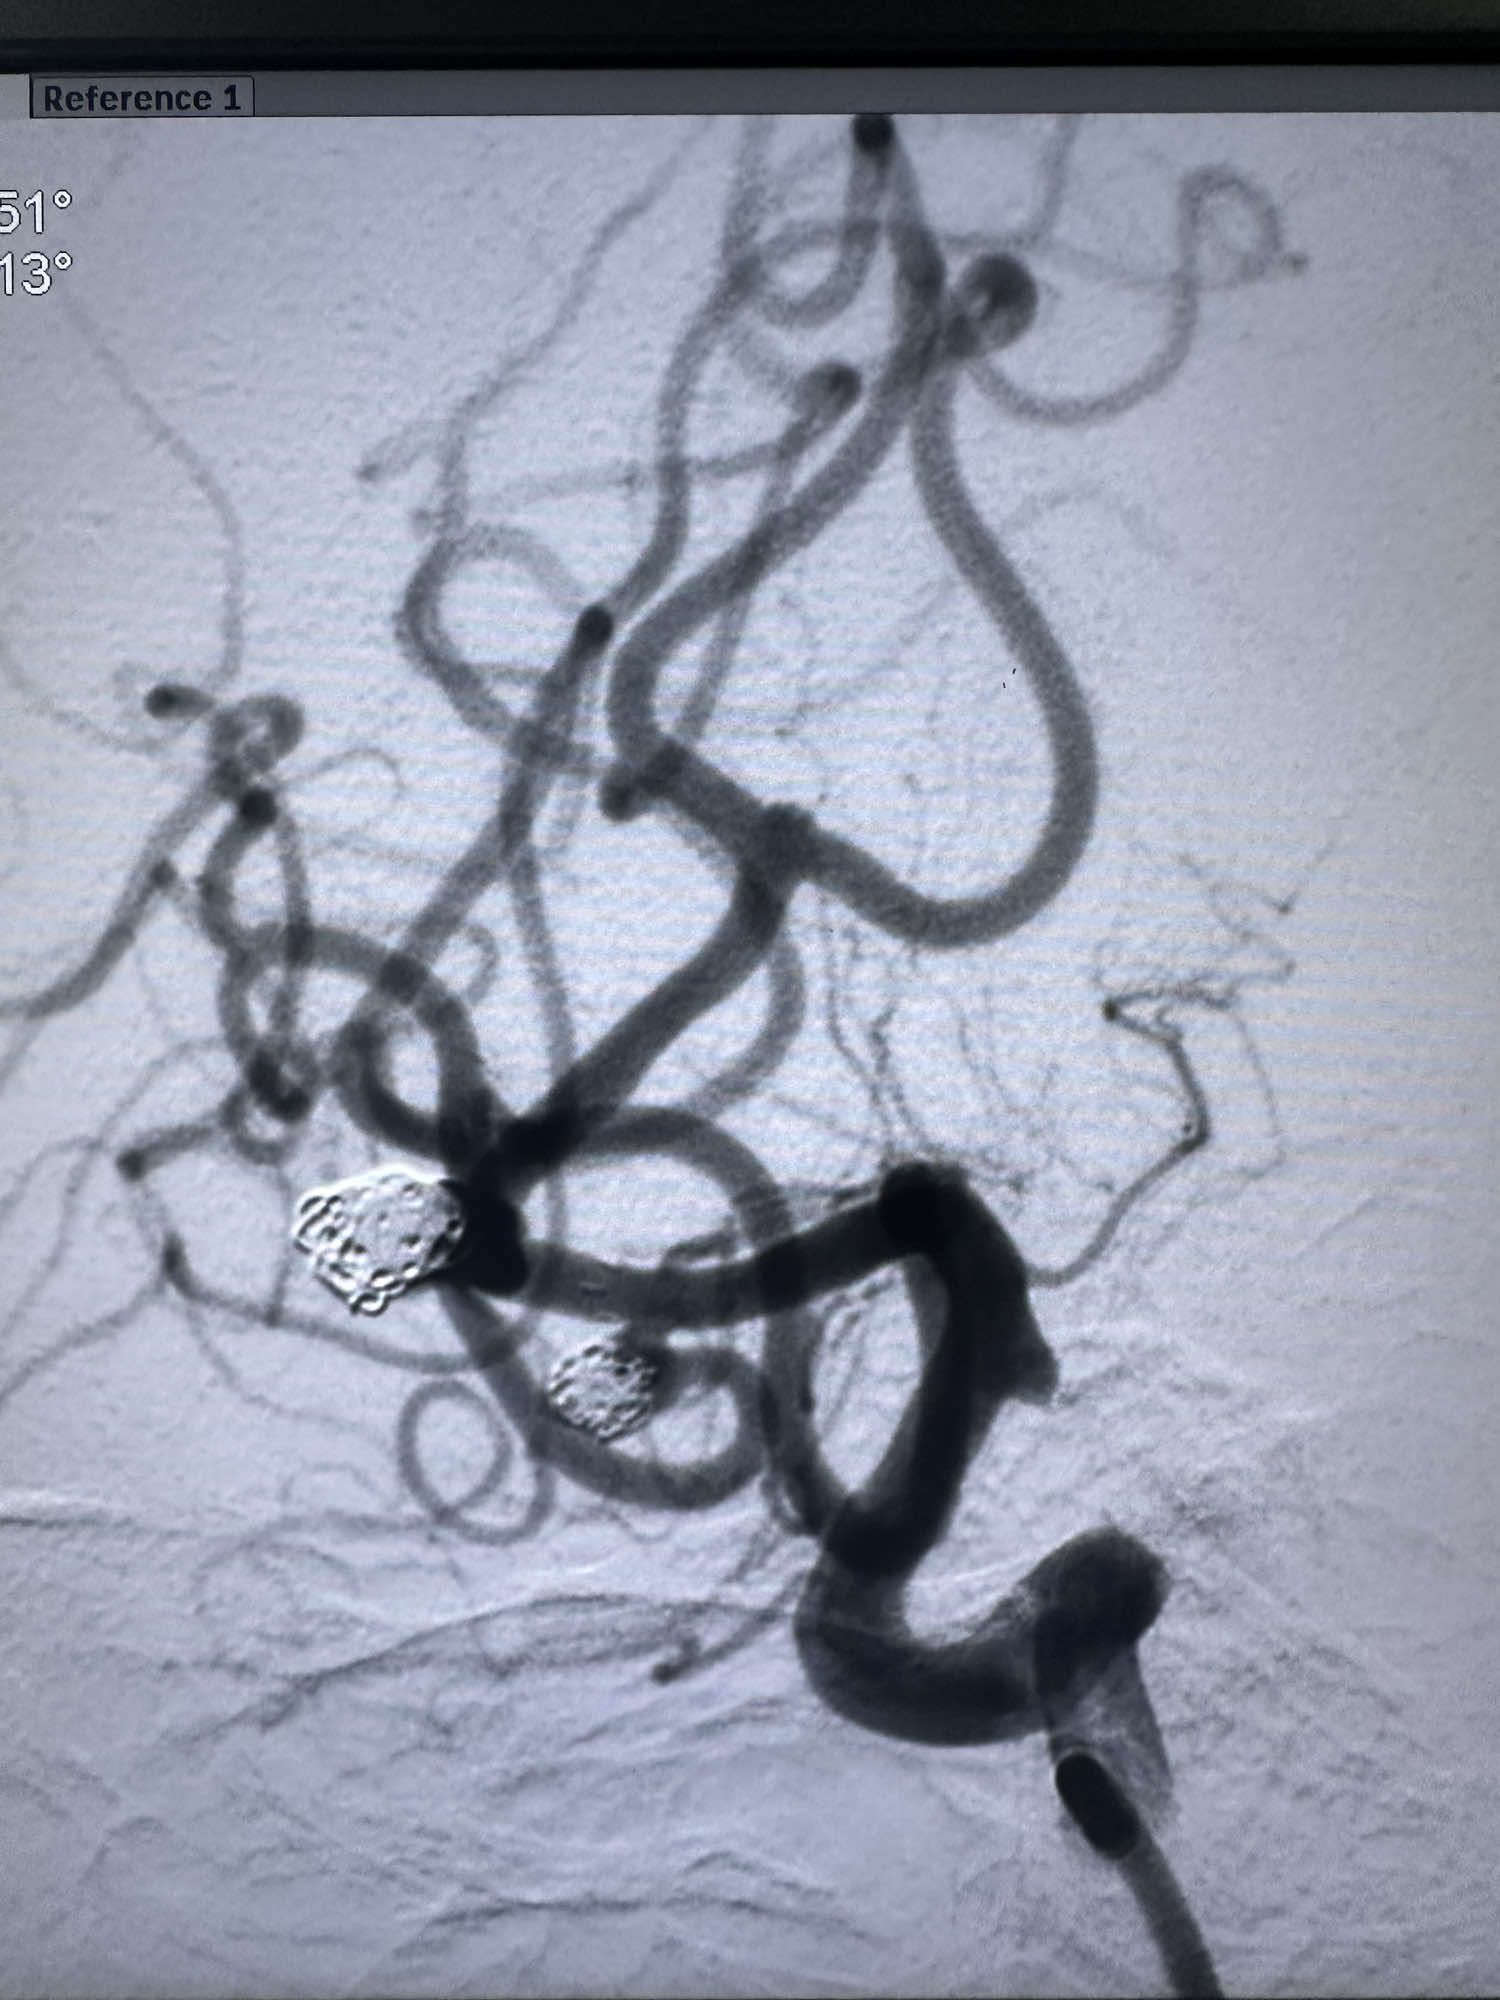

最后造影显示动脉瘤不显影

最后正位造影

侧位